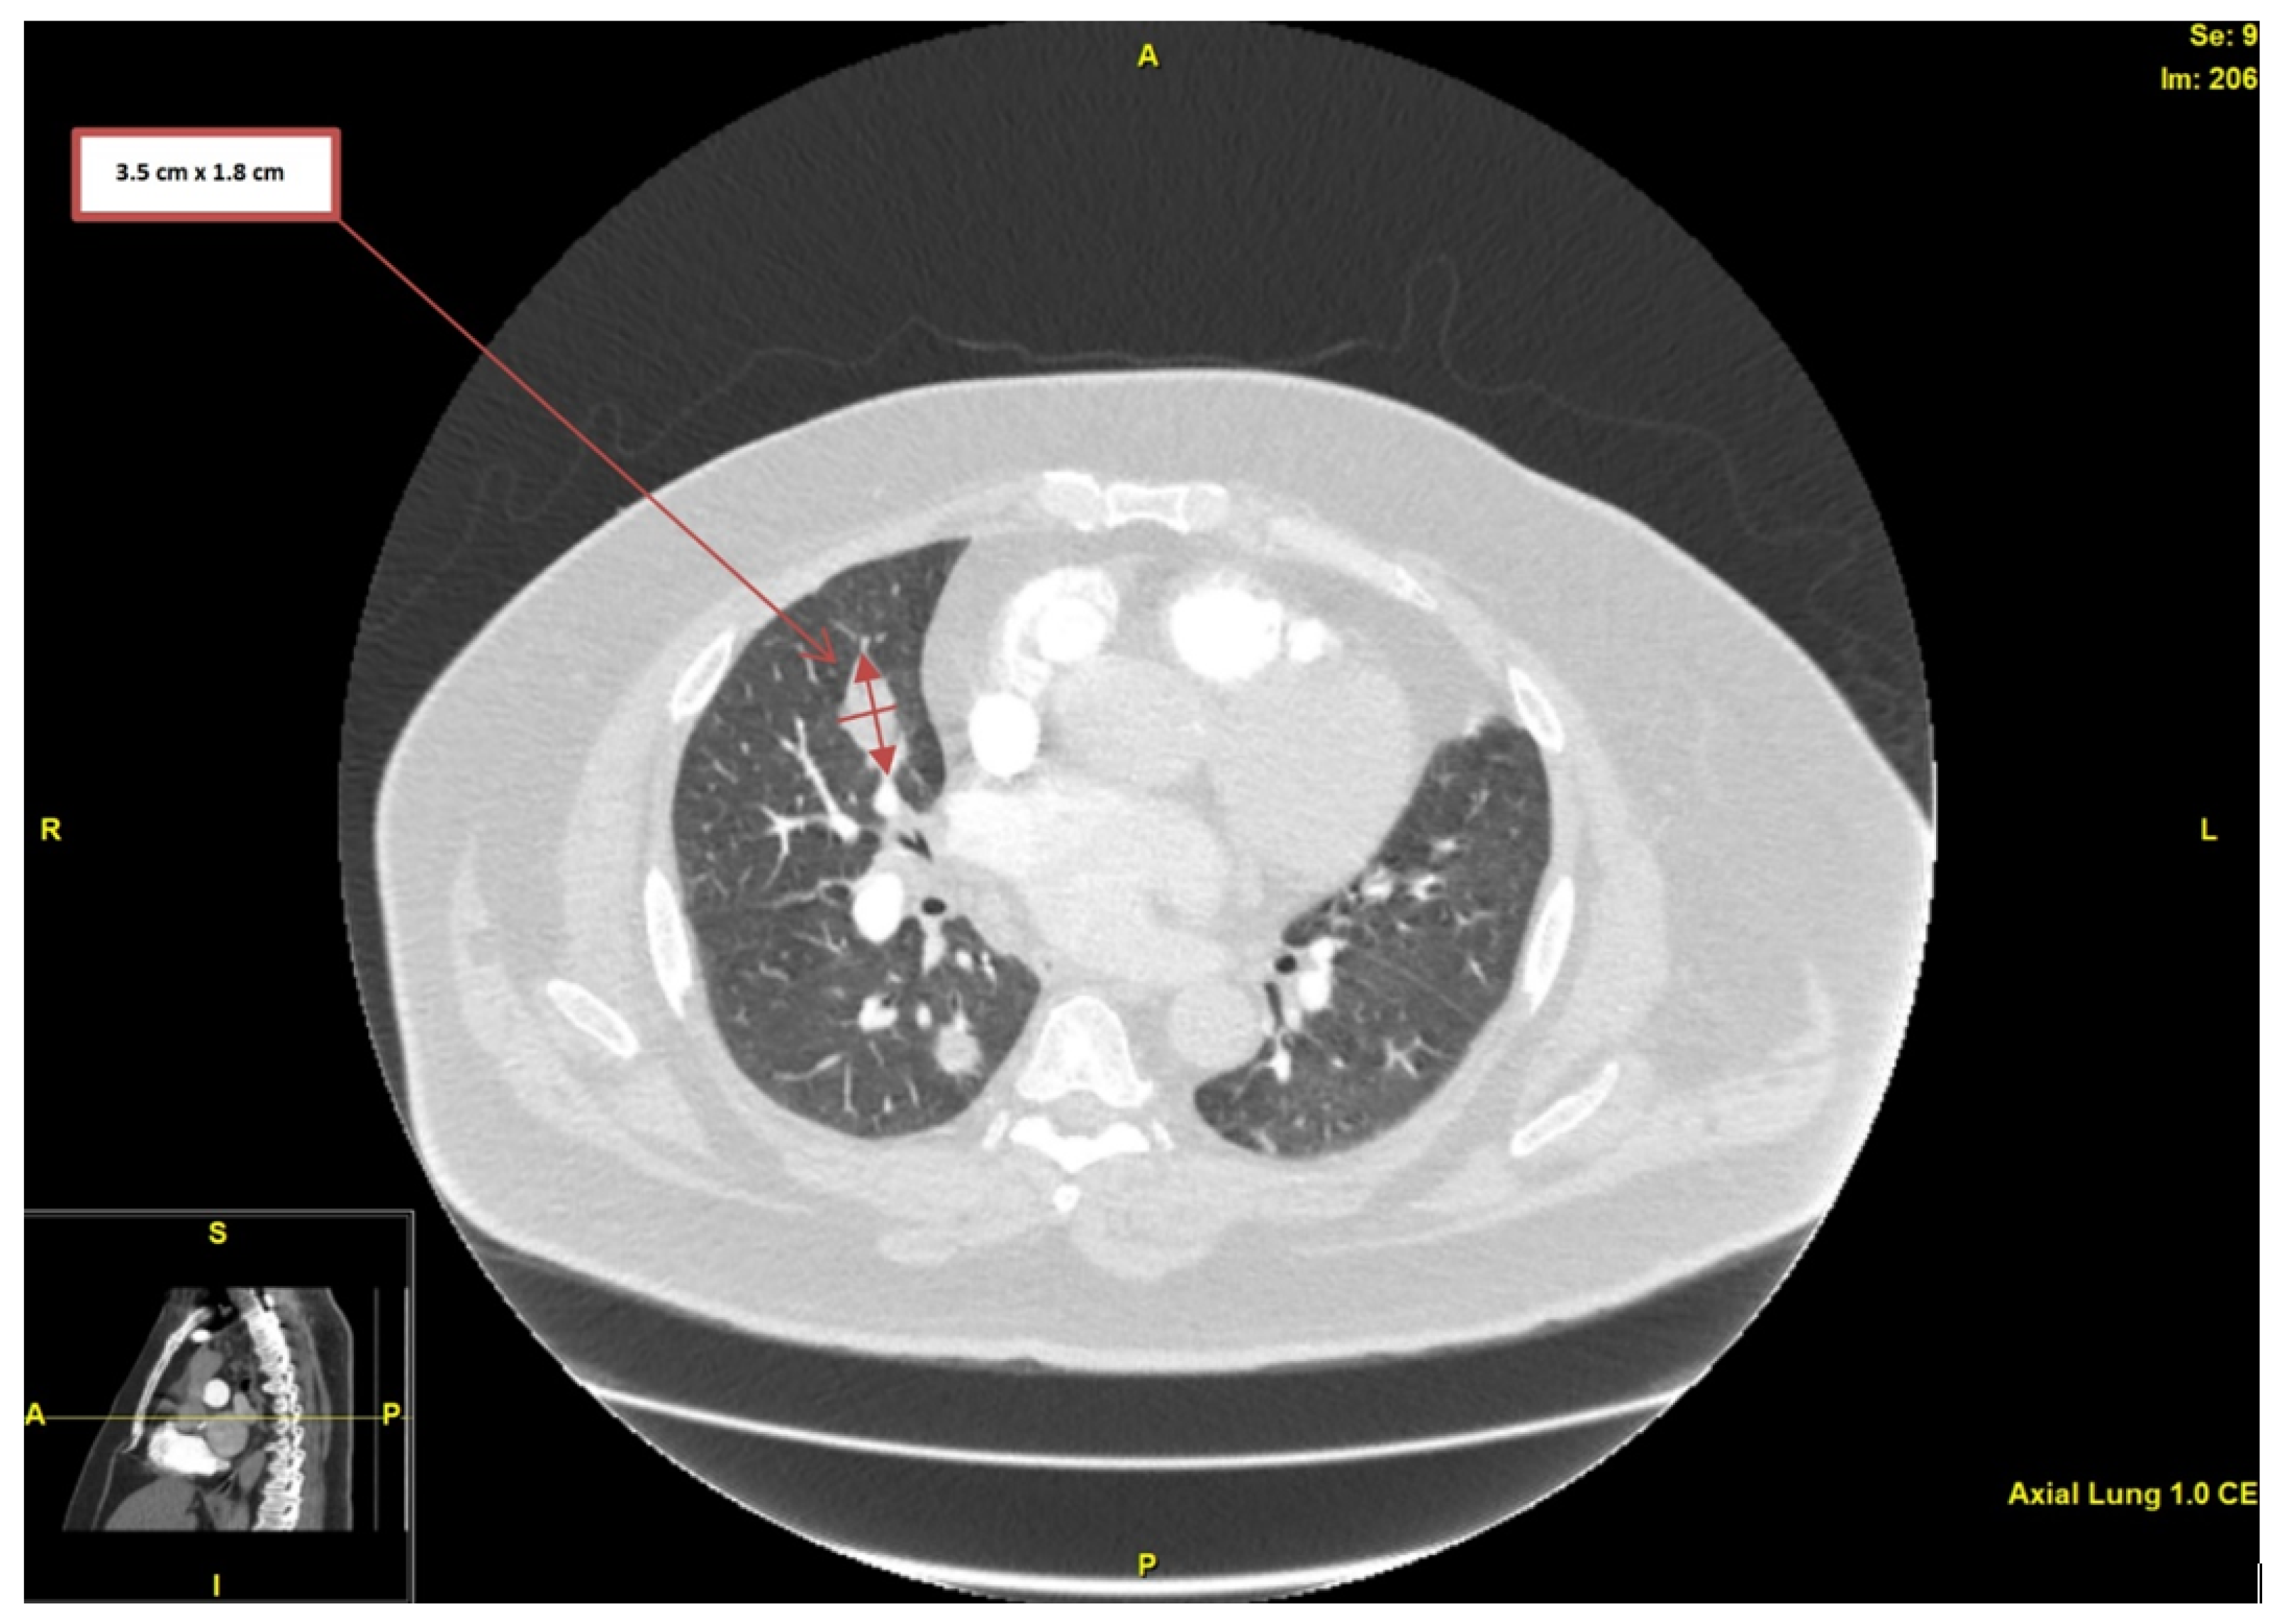

2. Case Presentation